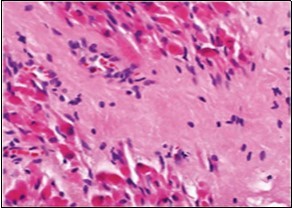

On microscopy, a collagen- rich, minimally cellular, fibrotic soft tissue nodule is exemplified which simulates a scar or conventional fibroma. The neoplasm is comprised of uniform, plump, fibroblastic or myo-fibroblastic cells encompassed in a collagen-rich stroma with infiltration and entrapment of skeletal myocytes 5, 6. Cogent histological examination depicts replacement of muscle fibres and muscle mass with fascicles of fibrous tissue comprised of mature fibroblastic cells, thereby conferring fibrosis 6. Figure 1, Figure 2, Figure 3, Figure 4, Figure 5, Figure 6, Figure 7, Figure 8.

Figure 2.Fibromatosis colli demonstrating fascicles of fibroblasts and myo-fibroblasts within an abundant collagenous stroma and several mature myocytes 10.